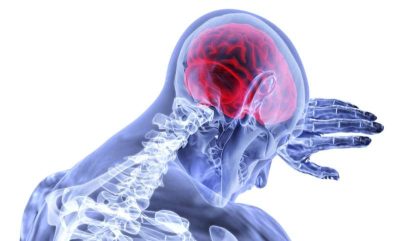

“Farmaci per la nausea, noti come antiemetici antidopaminergici (ADA), che sono ampiamente utilizzati per alleviare la nausea e il vomito causati, ad esempio, da emicrania, chemioterapia o radioterapia e dopo l’intervento chirurgico, sono associati a un aumentato rischio di ictus ischemico”, rileva uno studio pubblicato da The BMJ oggi.

I risultati mostrano che tutti e tre gli ADA studiati (Domperidone, Metopimazina e Metoclopramide) erano associati a un aumento del rischio, soprattutto nei primi giorni di utilizzo, ma l’aumento più elevato è stato riscontrato per Metopimazina e Metoclopramide. I ricercatori suggeriscono che la potenziale azione degli ADA sul flusso sanguigno al cervello potrebbe spiegare questo rischio più elevato.

Dopo aver tenuto conto di fattori potenzialmente influenti, i ricercatori hanno scoperto che i nuovi utilizzatori di ADA potrebbero avere un rischio di ictus 3 volte maggiore subito dopo l’inizio del trattamento. Ulteriori analisi per età, sesso e storia di demenza hanno mostrato risultati simili, con gli uomini a rischio più alto (un aumento di 3,59 volte). Il rischio sembrava aumentare per tutti gli ADA, l’aumento più alto è stato riscontrato per Metopimazina (un aumento di 3,62 volte) e Metoclopramide (un aumento di 3,53 volte), entrambi farmaci che attraversano la barriera ematoencefalica.

E sebbene siano necessarie ulteriori ricerche di inferenza causale per confermare questa associazione in altri contesti, suggeriscono che “il rischio più elevato riscontrato per i farmaci che attraversano la barriera ematoencefalica suggerisce un potenziale effetto centrale, possibilmente attraverso un’azione sul flusso sanguigno cerebrale”.